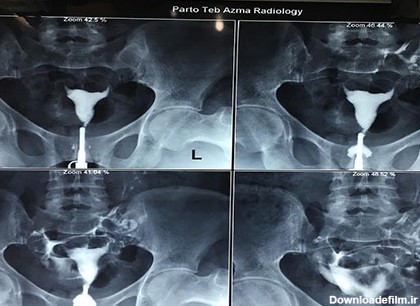

عکس رنگی رحم بدون درد؛ هیستروسالپنگوگرافی برای مشاهده داخل رحم و لوله های فالوپ استفاده می شود. می تواند نشان دهد که داخل رحم اندازه و شکل طبیعی دارد یا خیر.